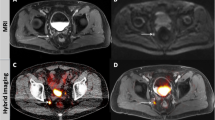

Fig. 4

68Ga-PSMA PET/CT images (a, b) and PET/MRI (c, d) in patient 8. This is another example of the benefits of late PET imaging (improved tracer uptake) compared to MRI (improved anatomical correlation; white arrows lymph node). a CT image without contrast medium, b PET/CT fusion image, c MR image (T1 with contrast medium and fat saturation), d PET/MRI fusion image. (JPEG 54 kb)